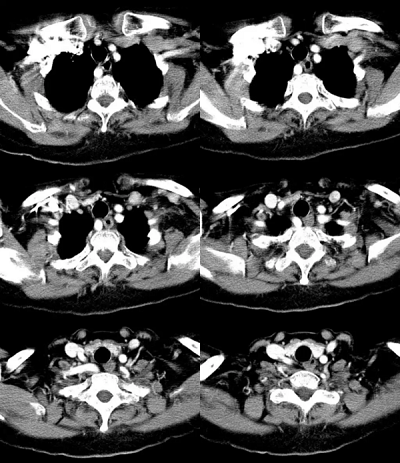

当时检查结果显示,周先生左右侧颈动脉均有不同程度斑块的出现。右侧锁骨下动脉起始部后壁可见大小约0.9*0.3厘米混合回声斑块,右侧颈外动脉起始部后壁可见大小约1.1*0.17厘米混合回声斑块,左侧颈外动脉起始部后壁可见大小约1.1*0.21厘米的回声斑块。

CDFI结果:斑块处血流信号充盈缺损,频谱形态及血流速度未见明显异常。双侧颈总、颈内、外动脉内径正常,内中膜增厚不光滑。

监测颈动脉斑块情况,在当地医院检查后,右侧锁骨下动脉的斑块已经基本消失,左右两侧的斑块也变小了,医院的医生还问他在哪里治疗的,夸赞效果十分不错。